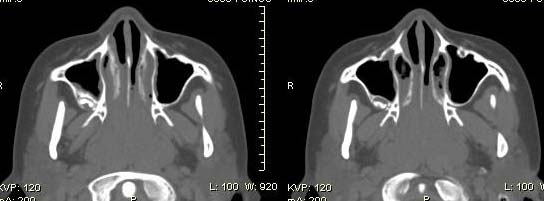

以下是引用随光逐影在2009-6-4 21:13:00的发言:[br]1)考虑鼻咽腺样体重度肥大。2)双侧鼻腔炎性改变。3)双侧上颌窦、双侧筛窦及左侧蝶窦炎症。

以下是引用zsl6918在2009-6-5 7:42:00的发言:[br]首先考虑鼻咽腺样体重度肥大,鉴别纤维血管瘤.强化有助明确.